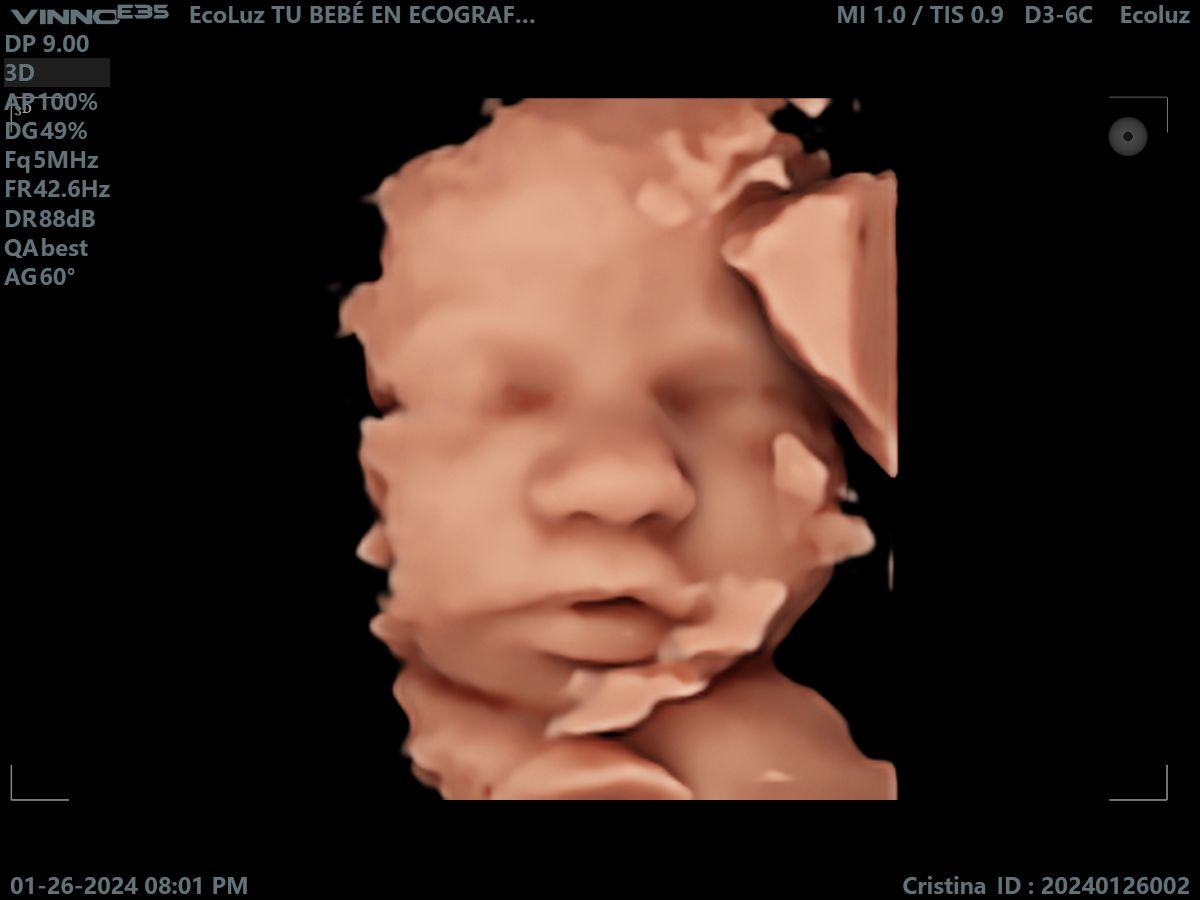

Sí, la eco de 30 semanas suele ofrecer imágenes muy definidas gracias al desarrollo avanzado del bebé. Sus rasgos están prácticamente formados y la experiencia es muy emocionante. En EcoLuz…

Dentro del tercer trimestre, la ecografía de 30 semanas es de las más recomendadas para ver el rostro con detalle. Un recuerdo perfecto antes del gran día. 💛

La ecografía 30 semanas embarazo fortalece el vínculo emocional. Ver su carita tan definida hace que el encuentro esté cada vez más cerca.